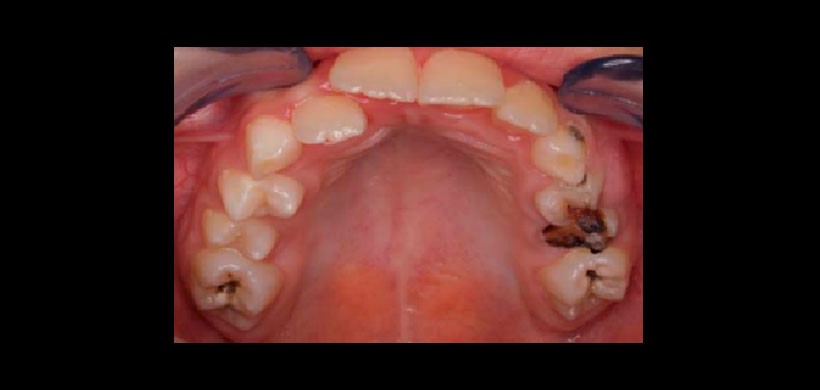

Fig 1. Caries de aparición temprana, es una enfermedad que altera la salud bucal en la primera infancia, conlleva a pérdidas prematuras dentarias y a problemas futuros de maloclusiones.